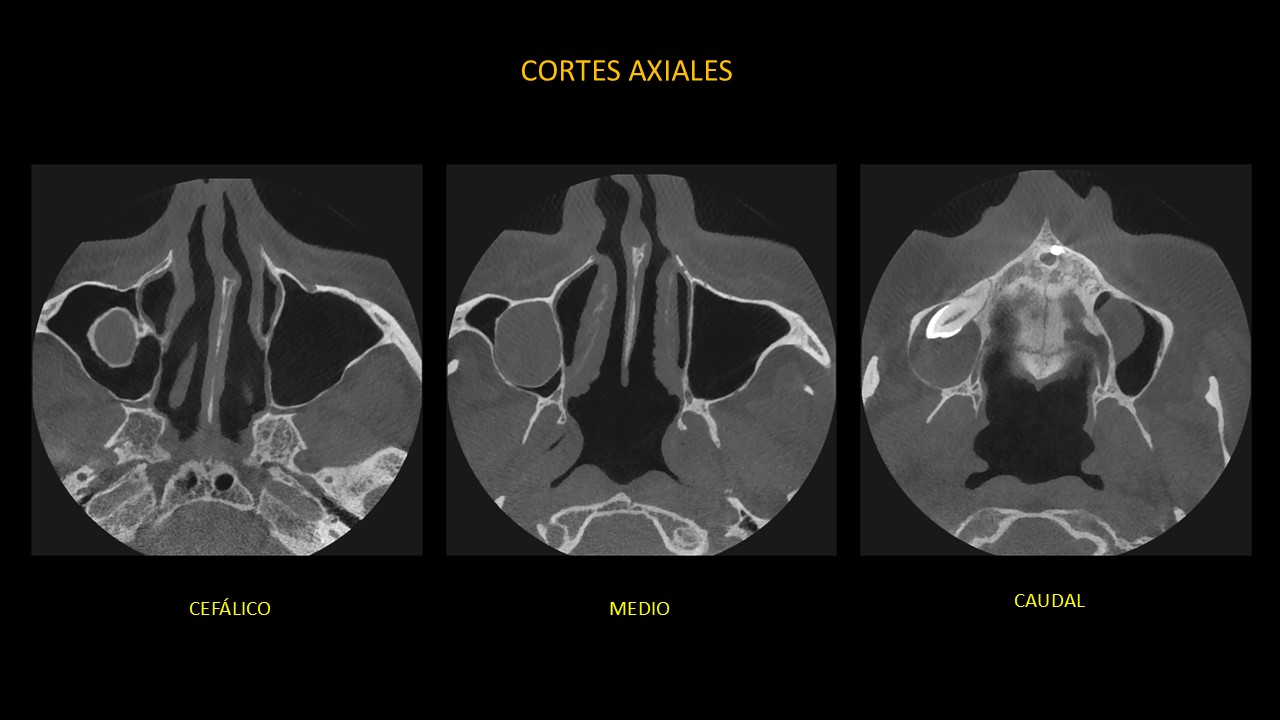

Figura 2

En cortes axiales (Figura 2), se confirma la presencia de una imagen isodensa peri coronaria, de límites definidos, de bordes parcialmente corticalizados y forma redondeada, en relación con el tercio cervical y corona de pieza 13.